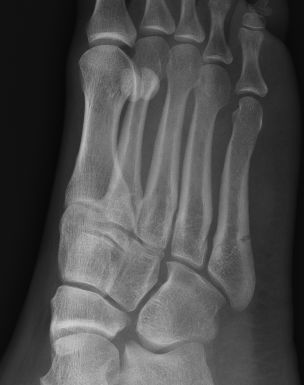

Xray

Zone 2 fractures

Union of zone 2 fracture with nonoperative care

Progression to nonunion of zone 2 fracture with nonoperative care

Zone 3 Fractures

Progression to nonunion of zone 3 fracture with nonoperative care